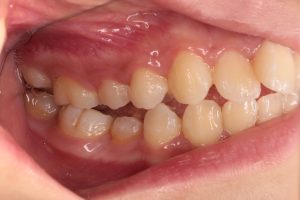

左の写真は上下の歯がかみ合っていない状態、右の写真は上下の歯がかみ合っている状態

右の写真のようにかみ合っているのが正常ですが、中心結節の突起が折れてしまいやすいので早めの処置が必要です。